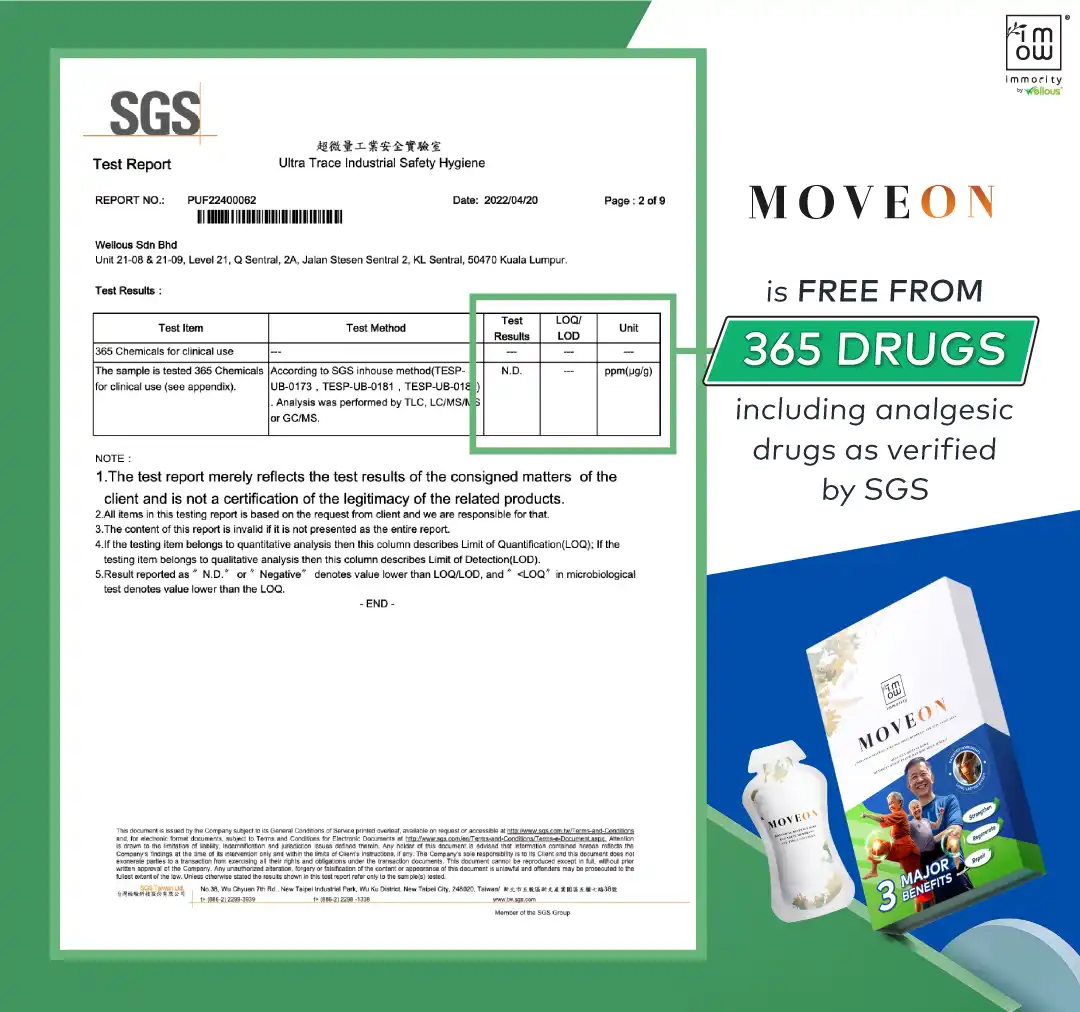

100% Safe & Natural. 33 Years Of R&D, Approved by HSA, SFA, SGS, MOH & HALAL certified.

- 100% Natural

- No Drugs, No Dependency

- No Heavy Metals or Steroids

- Certified HALAL, HSA, SFA, USA FDA

Moveon Liveon is made from 100% natural ingredients, free from steroids, chemicals, or side effects. They are certified by HSA, SFA, HALAL, and USA FDA, and are safe for long-term use with no known side effects.